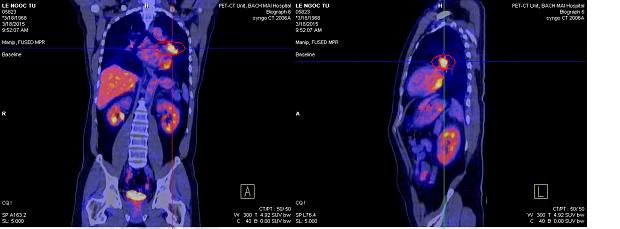

- Đốt sống C7 tăng hấp thu F-18 FDG, max SUV=3,6 (kích thước 1,2x1,3cm)

Hình 4. Hình ảnh PET/CT: tổn thương tăng hấp thu F18- FDG tại cột sống C7 nghĩ đến tổn thương thứ phát (vòng tròn đỏ)

- Bệnh nhân được chụp PET/CT đánh giá sau 6 đợt hóa chất

Hình 6. Hình PET/CT sau 6 đợt hóa chất: còn tổn thương tăng FDG ở thùy trên phổi T (kích thước 25x15mm), max SUV: 6,0

(vòng tròn đỏ)